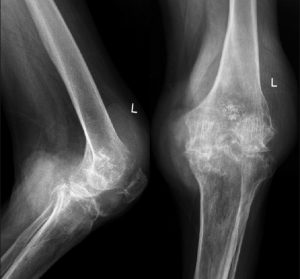

Диагноз выставляется на основании анамнеза, данных местного проявления, лабораторных исследований (повышение мочевой кислоты, признаки воспаления). Из инструментальных методов наиболее информативно МРТ, рентгенограмма, которые показывают признаки разрушения сустава при течении болезни 5-7 лет.